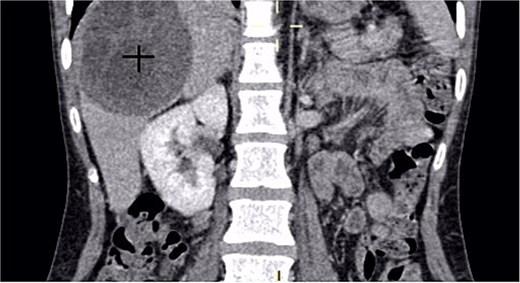

A 30-year-old woman, gravida 2 para 2, presented with a 10-day history of right upper quadrant (RUQ) abdominal pain. She had no significant medical or surgical history and denied systemic symptoms such as fever, weight loss, or fatigue. On examination, she was afebrile and hemodynamically stable, with a WHO performance status of 1. Abdominal palpation revealed localized tenderness in the RUQ. Laboratory investigations revealed mild leukocytosis (12 250/μL), Hb:10.8 g/dL, Plt:538000, TP:64%, Na:132 mmol/L, K:4.1 mmol/L, CRP:299 mg/L. Liver function tests showed GGT:36 U/L, PAL:46 U/L, ASAT:13 U/L, ALAT:6 U/L, total bilirubin:5 mg/L, direct bilirubin:3 mg/L. Urea and creatinine were 0.2 and 3.6, respectively. Contrast-enhanced CT revealed a large mass in the gallbladder bed, suspected to be a tubulo-papillary intracholecystic neoplasm (ICPN) (Figs 1 and 2), with an associated angiomatous liver lesion in segment III, hydatid cysts, and mild ascites. Exploratory laparotomy was performed, revealing a ruptured gallbladder tumor with extension into adjacent liver tissue and abdominal wall, and free biliary stones within the peritoneal cavity (Fig. 3).

Intraoperative image showing a ruptured gallbladder tumor with gallstones scattered within the abdominal cavity. The tumor exhibits extensive invasion of adjacent tissues, emphasizing the aggressive nature of undifferentiated gallbladder carcinoma.